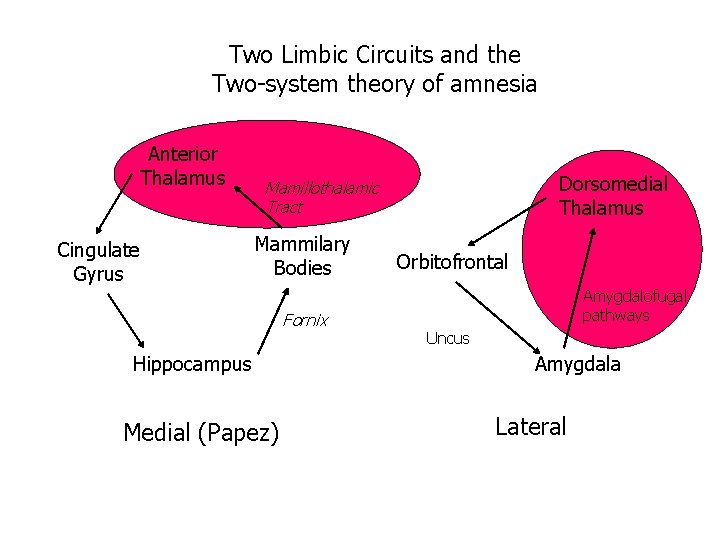

Two Limbic Circuits and the Two-system theory of amnesia Anterior Thalamus Cingulate Gyrus Dorsomedial Thalamus Mamillothalamic Tract Mammilary Bodies Orbitofrontal Amygdalofugal pathways Fornix Uncus Hippocampus Amygdala PRPH Medial (Papez) Lateral

Two Limbic Circuits and the Two-system theory of amnesia Anterior Thalamus Cingulate Gyrus Dorsomedial Thalamus Mamillothalamic Tract Mammilary Bodies Fornix Hippocampus Medial (Papez) Orbitofrontal Amygdalofugal pathways Uncus Amygdala Lateral